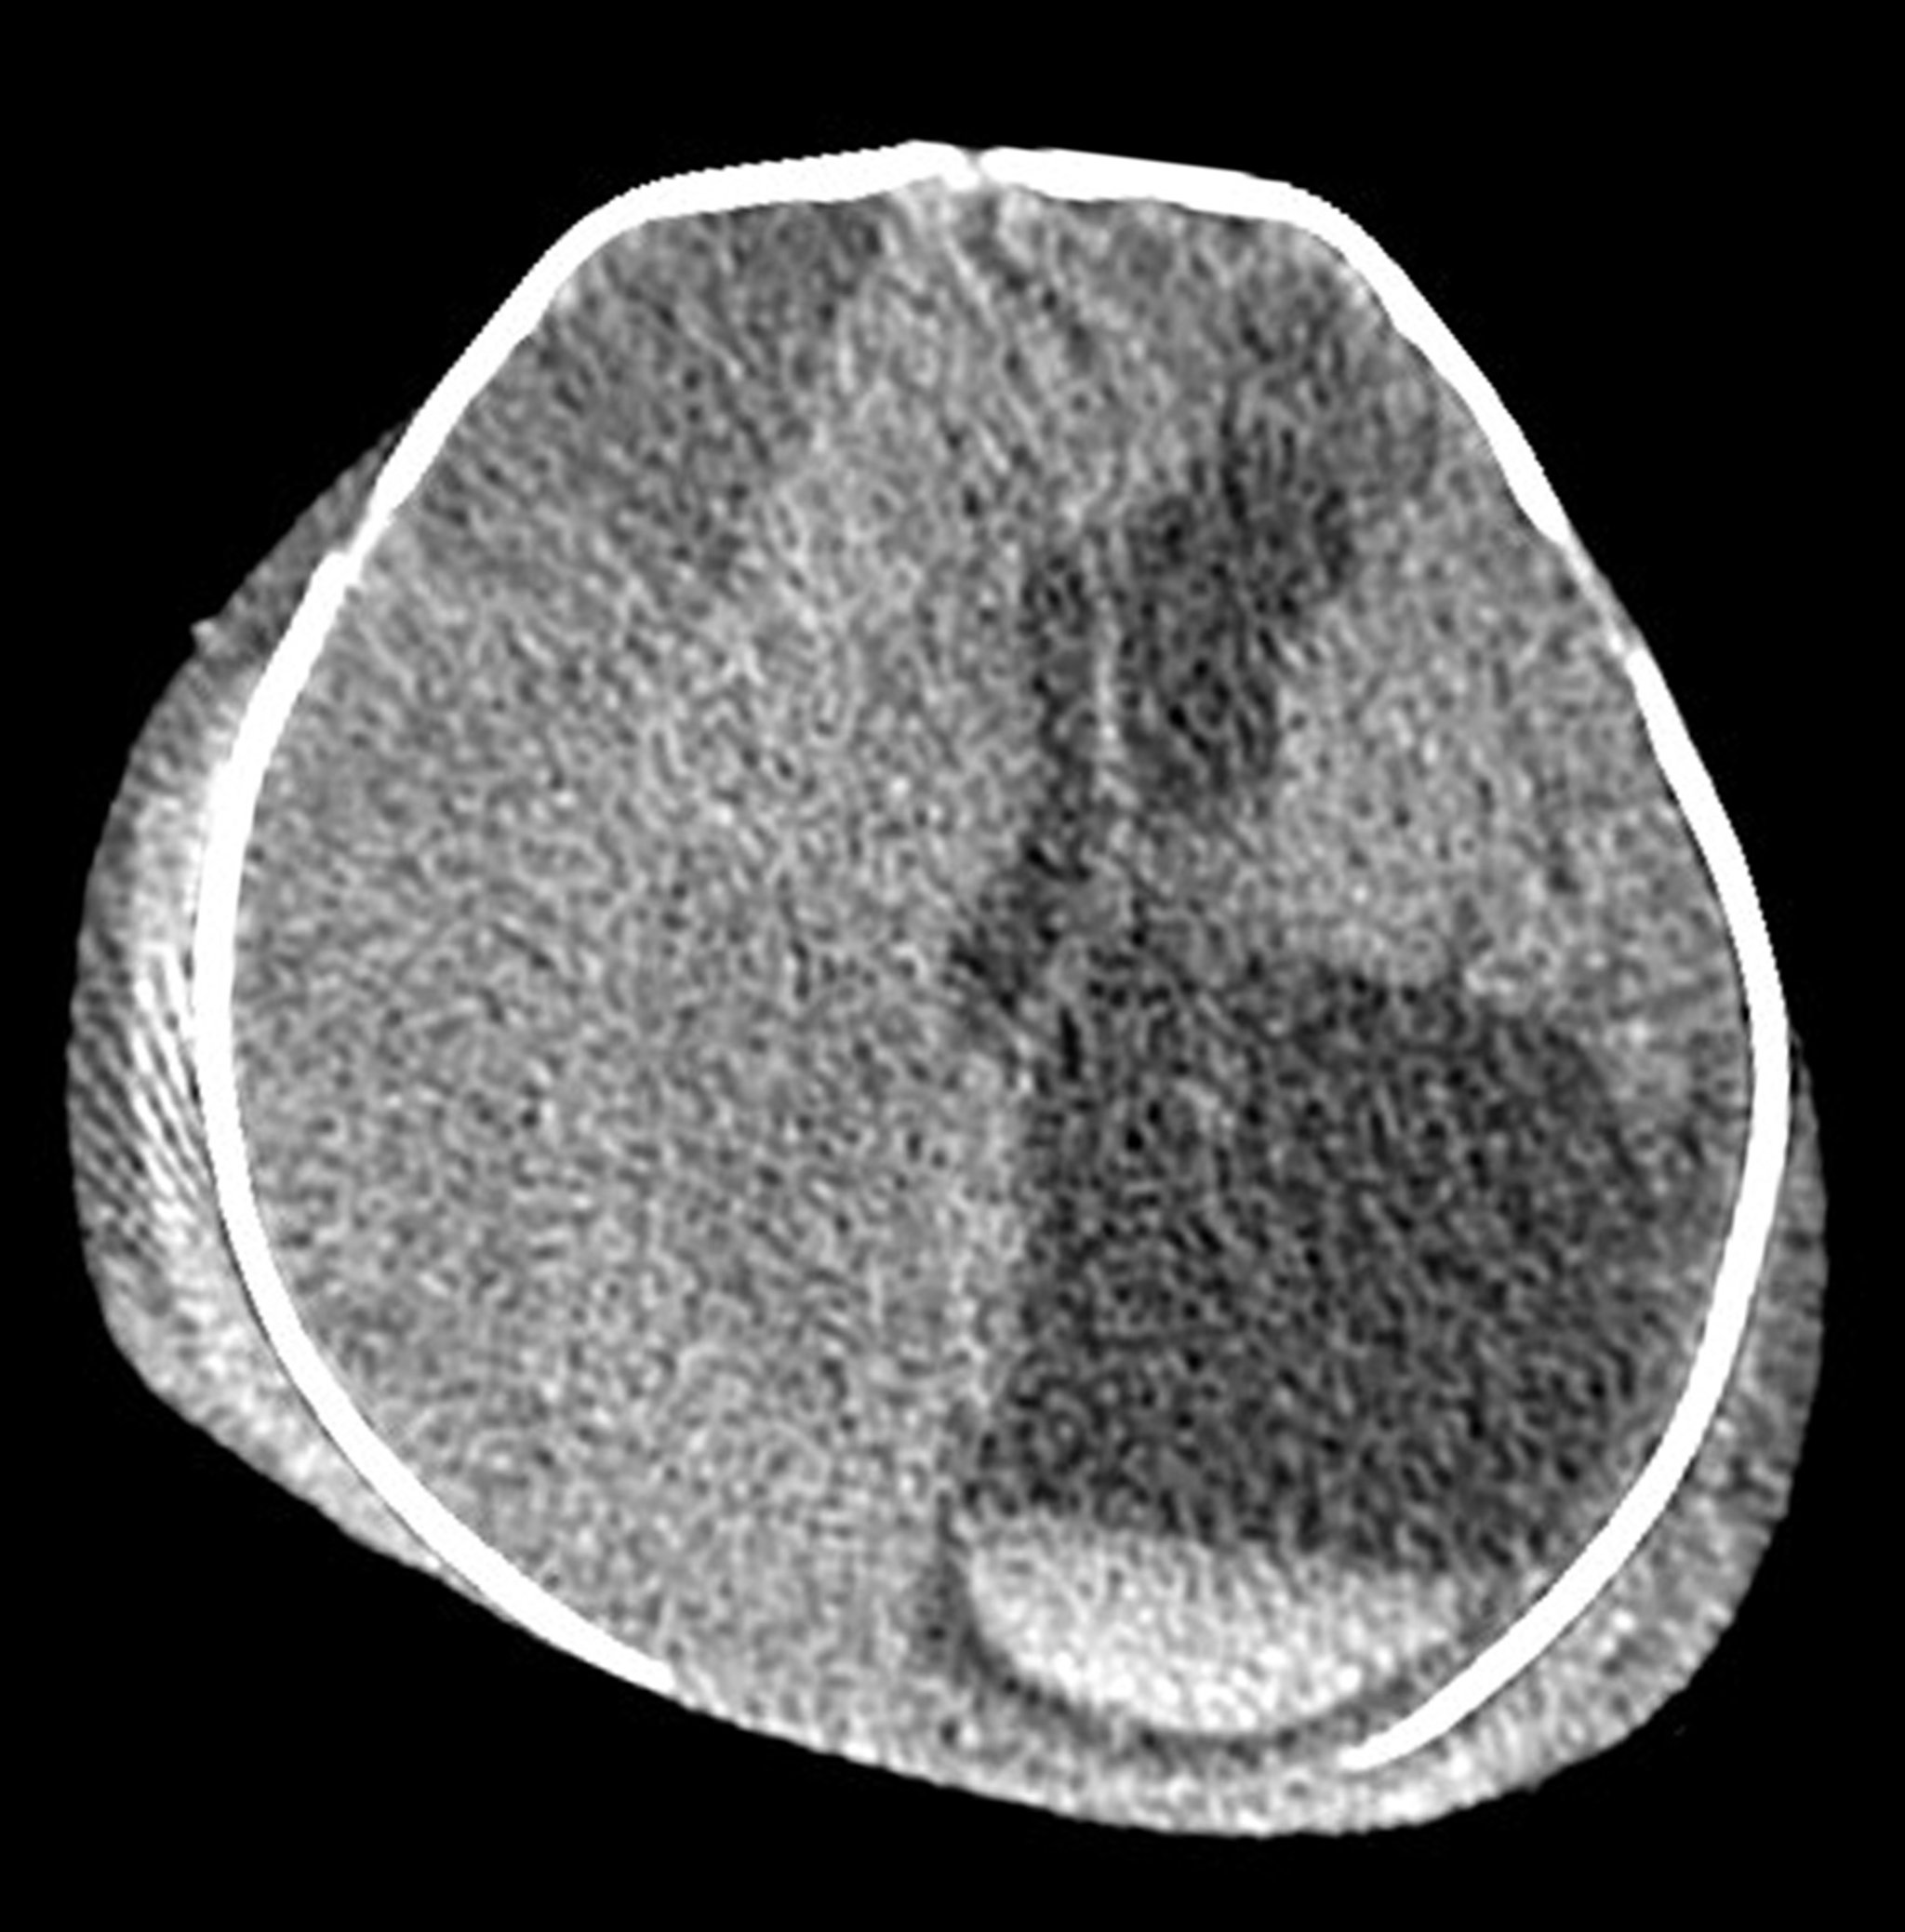

Extensive Birth Injuries in a Neonate (CT Scan)

This axial (cross-sectional) CT of the head in a neonate shows extensive extracranial and intracranial injury secondary to severe birth-related injury. There is bilateral swelling/hematoma formation in the scalp. There is a very large isodense (subacute) subdural hematoma along the right cerebral hemisphere, causing brain herniation across the midline. The hematoma results in enlargement of the left lateral ventricle. Acute blood layering in the bottom of the left lateral ventricle (white material with a straight line) is seen at the lower right aspect of the image.

Living Art Enterprises, LLC/SCIENCE PHOTO LIBRARY